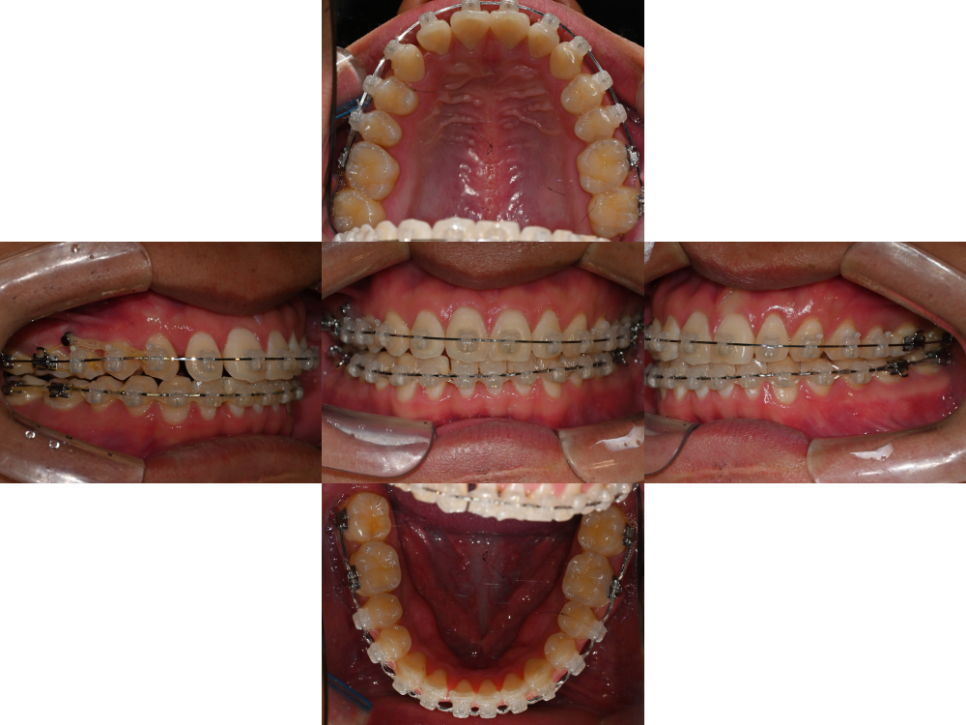

23.12.14

이 케이스의 경우

검사와 시뮬레이션을 통해

비발치 교정을 진행했습니다.

클리피씨 브라켓를 치면에 부착하고

오른쪽 윗니 주위에 미니 스크류 를 식립했는데요.

24.04.05

클리피씨 브라켓은

자연치의 이동 시 생기는 마찰력을 줄일 수 있어

통증의 정도가 경감될 수 있습니다.

더불어, 메탈에 비해

더 심미적이며 음식 끼임 정도가 적은데요.

24.08.28

이 덕분에 구강 위생 관리가

용이해진다는 특징이 있습니다.

동시에 정확한 치아 이동을 위해

오른쪽 위 쪽에 식립한

미니 스크류는 고정원의 역할을 담당하여

정확한 자연치 이동을 하는데

큰 도움을 줄입니다.